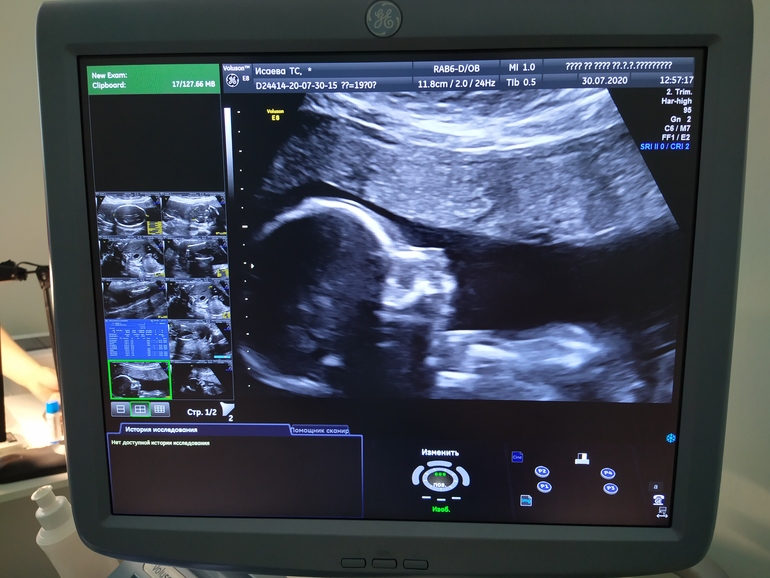

2 скрининг 🥰

Ой девчонки, прошла 2 скрининг, врач сказала все отлично, даже придраться не к чему 😄 наша звезДОЧКА осталась звезДОЧКОЙ 🥰🥰🥰 сидим правда на попе, но время есть, пускай вертится, весим 280 гр. С сердечком все ок, никаких пороков и тд. Была такой активной, по датчику лупасила ножками 😄😄😄

Не дала себя целиком сфоткать, постоянно отворачивалась спиной 😄 стесняшка 🥰